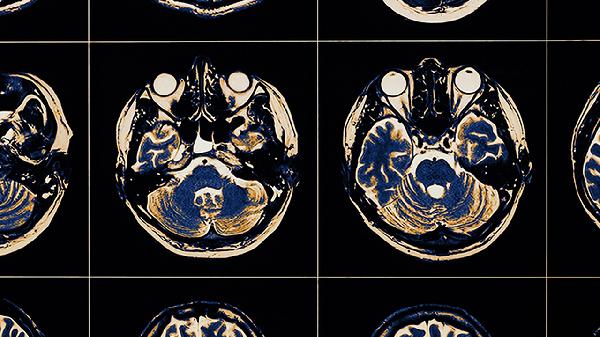

靜脈注射阿替普酶溶栓同時(shí)進(jìn)行血管內(nèi)介入的橋接治療,可顯著提高血管再通率。這種聯(lián)合方案對(duì)頸內(nèi)動(dòng)脈或大腦中動(dòng)脈近端等大血管閉塞效果明顯,再通率超過單純靜脈溶栓。治療需在發(fā)病4.5小時(shí)內(nèi)啟動(dòng),術(shù)前需通過CT灌注成像評(píng)估缺血半暗帶范圍。該技術(shù)對(duì)醫(yī)療設(shè)備及多學(xué)科協(xié)作要求較高,可能增加出血轉(zhuǎn)化風(fēng)險(xiǎn)。